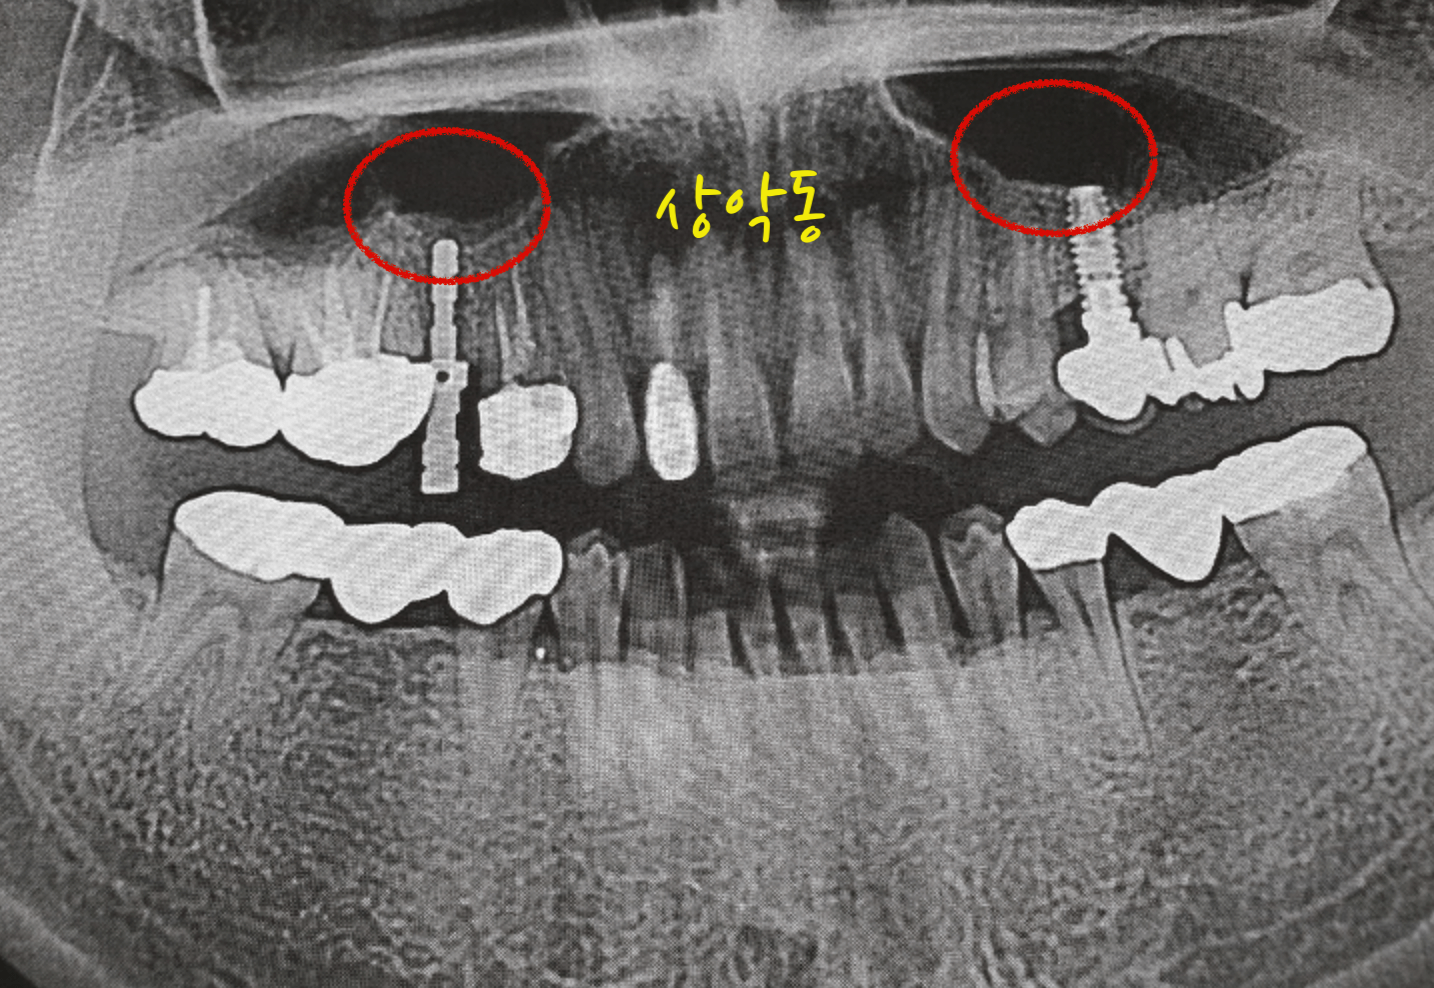

치아가 좋지 않다보니 임플란트를 심으면서 상악동 거상술을 두번 하게 되었습니다. 상악동은 아랫어금니 쪽이 아닌 윗어금니 쪽에서 코와 이빨사이에 빈공간을 이야기 합니다. 지금부터 상악동 거상술 비용 및 보험 청구 후기 경험을 공유 합니다.

상악동 거상술

상악동 거상술은 윗쪽 어금니와 코사이에 존재하는 부비동 공간에 그막을 살작들어서 파열되지 않게 임플란트를 삽입하기 위해 하는 시술입니다.

부비동은 코의 양쪽에 위치한 빈공기로 채워진 공간이며, 상악에서 상실된 어금니를 대체하는데 사용되는 치과 임플란트에 영향을 줄수 있습니다. 이부위의 뼈는 다른부위에 비해 얇아지는 경향이 있어 자연치를 발치한 후에는 뼈손실이 발생하는 경우가 많습니다.